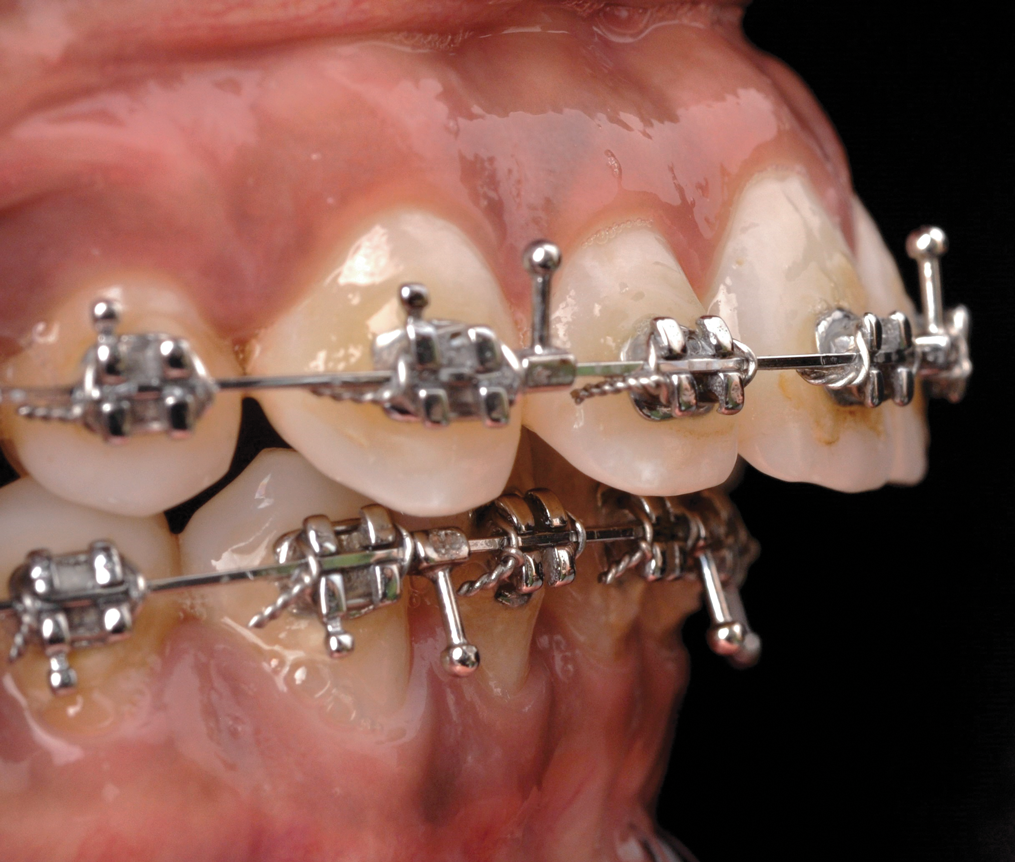

Fig 4. Miniplate in the lower posterior used to perform alignment of a very crowded lower arch during preparatory orthodontics for a class III adult female patient requiring double jaw surgery. Fig 4: Crowding present before presurgical orthodontics. Fig 5: Crowding corrected using the miniplate as anchorage.

Figure 4

Fig 5. Miniplate in the lower posterior used to perform alignment of a very crowded lower arch during preparatory orthodontics for a class III adult female patient requiring double jaw surgery. Fig 4: Crowding present before presurgical orthodontics. Fig 5: Crowding corrected using the miniplate as anchorage.

Figure 5